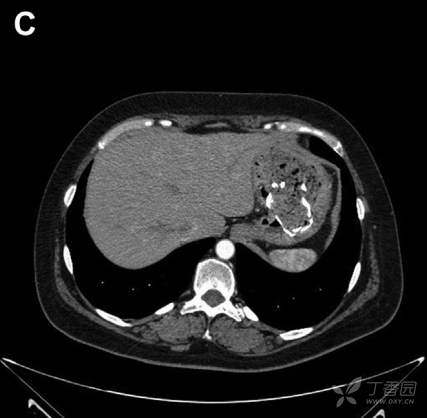

术后患者出现恶心、呕吐、食欲减退、乏力及发热,病情逐渐加重。术后2月腹部CT提示胰瘘及左侧腹壁局限性脓肿,遂给予针对性治疗。但患者全身情况进一步恶化,出现上腹痛、恶心呕吐、食欲减退及体重下降(超过30Kg)。6个月后复查CT提示胃内幽门前区团块状物质,内含高密度线状影(图B,C)。

请问:诊断是什么?

A 手术异物遗留 B 胃肿瘤 C 胃脓肿钙化 D 胰瘘侵及胃